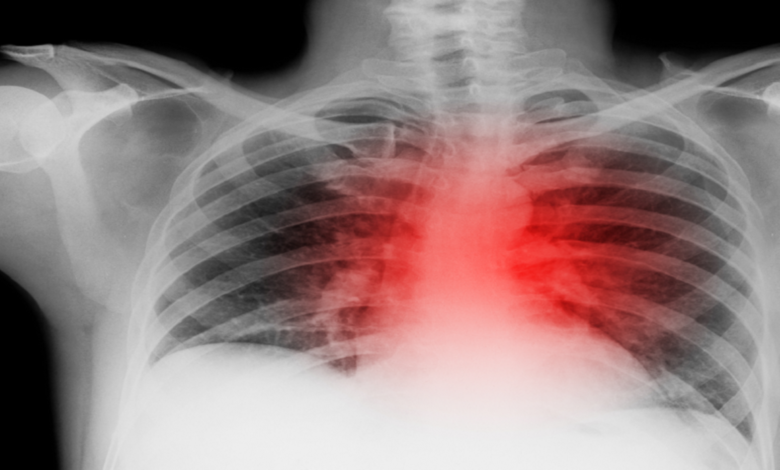

فيتامين B3.. علاج فعال لمرضى الانسداد الرئوي

توصل فريق من العلماء إلى أن تناول جرعة طبية من فيتامين محدد يمكن أن يُسهم بتقليل الالتهابات وتحسين نوعية حياة مرضى الانسداد الرئوي المزمن (COPD).

وفي دراسة أجريت في كوبنهاغن، تم إعطاء 20 مصابا بمرض الانسداد الرئوي المزمن 4 أقراص يوميا تحتوي على جرعات أعلى من فيتامين B3، مقارنة بما هو موجود عادة في المكملات الغذائية. وأظهرت النتائج أن هؤلاء المرضى شهدوا تحسنا ملحوظا بتقليل الالتهابات في رئاتهم.